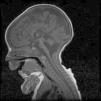

Caso 2Varón. Parto eutócico tras 39 semanas de embarazo, con ecografías prenatales normales. Apgar 8/9. No precisó reanimación en paritorio. Antropometría neonatal: P 2.560g (<p5), L 46,7cm (p10-25), PC 32,5cm (<p5). El cuadro clínico fue similar al de su hermana fallecida, precisando ventilación mecánica y alimentación enteral por SNG. Cariotipo 46, XY. La RM cerebral evidenció la presencia de hipoplasia de puente y cerebelo, que era compatible con el diagnóstico de HPC tipo 1 (fig. 1). Falleció a los 41/2 meses de vida por fracaso cardiorrespiratorio. Los estudios anatomopatológicos post mortem (médula espinal y músculo) fueron compatibles con atrofia muscular espinal y a nivel de cerebelo se encontró disminución de las células de Purkinje, de la capa granulosa y gliosis. El estudio molecular identificó la misma mutación (c.92G>C) en homocigosis en el gen EXOSC3, lo que confirmó el diagnóstico clínico. Ambos padres eran portadores heterocigotos de la mutación.